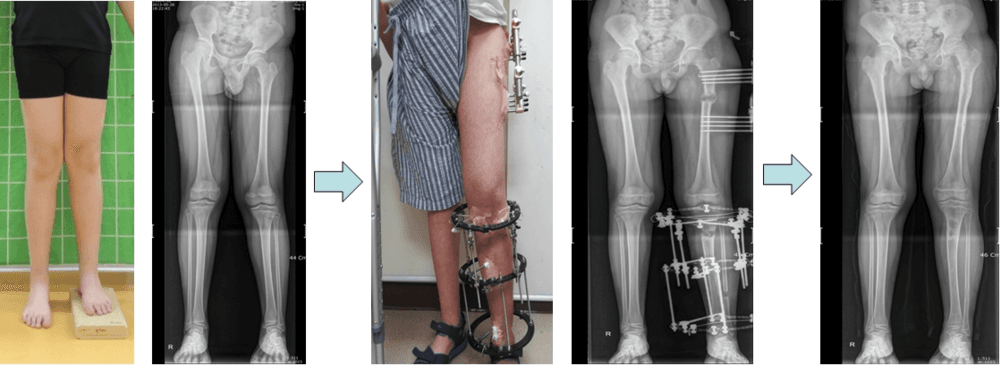

연골무형성증환자의 하지연장